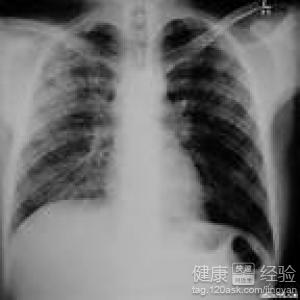

肺動脈栓塞是指由於內源性或外源性的栓子堵塞肺動脈主干或分支,引起肺循環障礙的臨床和病理生理綜合征。我姑姑就得了肺動脈栓塞末梢堵塞症,一開始得這個病的時候她非常的苦惱,後來在大家的建議下,去一家醫院就診。現如今已於今完全的康復了。非常感謝醫生的幫助,很多朋友都不知道得了肺動脈栓塞末梢堵塞症該怎麼辦下面我就來跟大家分享一下我的經驗。